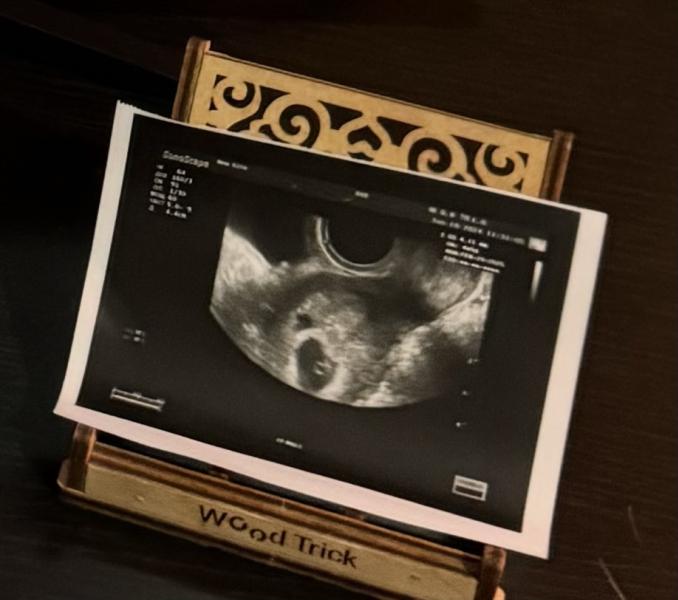

Вчера была на узи.

Видно два плодных яйца. У первого уже забилось сердечко, увидели с мужем на узи. Трепет не передать словами.

Второй был под вопросом, но он тоже подрос и его стало видно, но он как-будто запаздывает.

У первого получается 5,5 нед, а у второго гинеколог ставит «4 нед?»